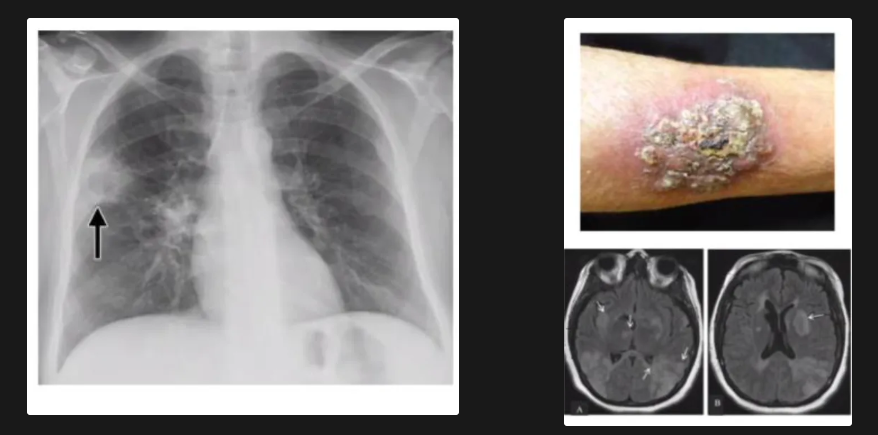

Manifestaciones clínicas de Coccidioidomicosis

A

• La mayoría son asintomáticos

• Primaria: pseudogripal, puede haber complejos inmunes

• Secundaria: nódulos, cavernas o neumopatía progresiva

• Diseminada 1%. Mortalidad del 90% (Piel, hueso, meninges y articulaciones)

Formas diseminadas inmunocomprometidos

- secundaria - pulmones, meninges & piel

-primaria - solo eritema multifrome/geografico